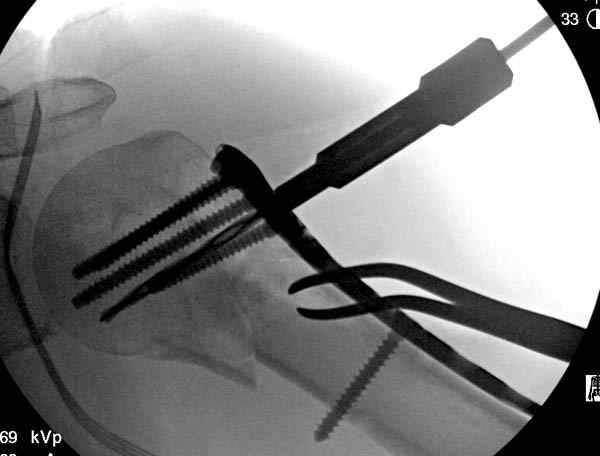

Рентгенограммы действительно с дефектом укладки, но интраоперационная репозиция, можете поверить, была удовлетворительная как в акcиальной, так и в сагиттальной плоскостях. Интраоперационная рентгенограмма прилагается, хотя укладка тоже на ахти. По тактике - разделяю Ваше мнение об отсутствии необходимости реостеосинтеза, а тем более об эндопротезировании, хотя это все было предложено пациентке ведущими ортопедами-травматологами России.

Для облегчения рентгенологического контроля во время операции мы применяем полусидячее, так называемое положение “beach chair” на операционном столе. Наши столы позволяют поднять ножной конец до необходимой высоты, только надо усадить больного к ножному концу стола.

Ошибки встречаются тогда, когда удовлетворяются только одной проекцией рентгена.

Здесь пример открытой репозиции 57 летнего с переломом плеча (1,2) смещение обнаружено на интероперационном снимке. При нормальной прямой проекция (3) угловое смещение обнаружили в аксиальной проекции (4)